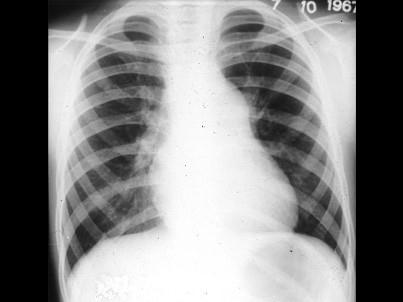

问题 男孩,8岁。体检时发现胸骨左缘第2肋间有粗糙喷射性全收缩期杂音,向颈部传导,肺动脉瓣区第2音减弱。经右心导管检查,证实为中度肺动脉瓣狭窄。进行X线检查,如图所示,下列哪一项不是特点 ( )

选项 A、肺动脉总干膨出 B、肺血减少,肺野清晰 C、右心室有不同程度增大 D、肺动脉段多平直 E、有时右心房增大

答案 D